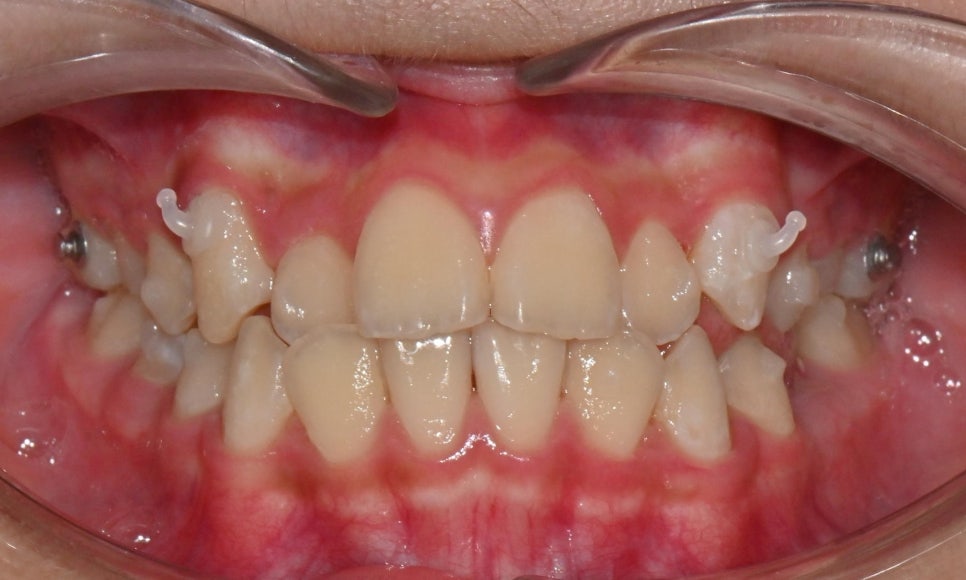

그러나 본 환자와 같이 제3급 부정교합 양상이 심하지 않은 경우에는 인비절라인 퍼스트 장치로는 악궁의 확장과 치아 배열을 얻고, 페이스 마스크로 위턱뼈의 성장을 촉진시키는 결과를 기대할 수 있습니다.

위 사진과 같이 송곳니 부위에 페이스 마스크를 착용하기 위한 고무줄을 걸 수 있는 고리를 부여하였습니다. 하루 8~10시간 정도 밤에 잘 때 착용하도록 함으로써 성장이 진행될 때 일종의 유지장치 개념으로 위턱뼈의 성장을 자극할 수 있도록 하였습니다.

이와 같이 인비절라인과 페이스 마스크 또는 무턱치료(Invisalign MA or MAOB)를 병행할 경우 턱뼈의 성장을 촉진시킴과 동시에 치아 배열을 같이 진행할 수 있다는 장점이 있습니다. 물론 모든 케이스에서 이러한 치료를 병행할 수 있는 것은 아니기 때문에 교정치과에서 정밀검진을 통해 먼저 현재의 상태를 정확하게 파악하고 상담하시는 것이 필수입니다.